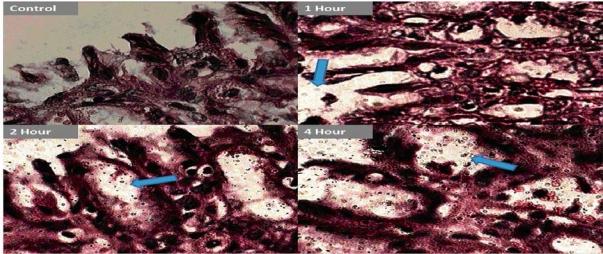

The present study has been undertaken to apply the concept of nanoparticulate mucopenetrating drug delivery system for complete eradication of Helicobacter pylori (H. pylori), colonised deep into the gastric mucosal lining. Most of the existing drug delivery systems have failed on account of either improper mucoadhesion or mucopenetration and no dosage form with dual activity of adhesion and penetration has been designed till date for treating H. pylori induced disorders. In the present study, novel chitosan-alginate polyelectrolyte complex (CS-ALG PEC) nanoparticles of amoxicillin have been designed and optimized for various variables such as pH and mixing ratio of polymers, concentrations of polymers, drug and surfactant, using 3(3) Box-Behnken design. Various studies like particle size, surface charge, percent drug entrapment, in-vitro mucoadhesion and in-vivo mucopenetration of nanoparticles on rat models were conducted. The optimised FITC labelled CS-ALG PEC nanoparticles have shown comparative low in-vitro mucoadhesion with respect to plain chitosan nanoparticles, but excellent mucopenetration and localization as observed with increased fluorescence in gastric mucosa continuously over 6 hours, which clinically can help in eradication of H. pylori.

本研究旨在应用纳米颗粒黏液穿透药物递送系统的概念,以彻底根除深入定植于胃黏膜内层的幽门螺杆菌(H. pylori)。大多数现有的药物递送系统由于黏膜黏附不当或黏液穿透不足而失败,迄今为止尚未设计出具有黏附与穿透双重活性的剂型来治疗幽门螺杆菌引起的疾病。在本研究中,采用三水平三因素的Box-Behnken设计,针对pH值、聚合物混合比例、聚合物浓度、药物浓度和表面活性剂浓度等变量,设计并优化了阿莫西林的新型壳聚糖-海藻酸盐聚电解质复合物(CS-ALG PEC)纳米颗粒。对纳米颗粒进行了粒径、表面电荷、药物包封率、体外黏膜黏附以及在大鼠模型上的体内黏液穿透等各项研究。优化后的异硫氰酸荧光素(FITC)标记的CS-ALG PEC纳米颗粒与普通壳聚糖纳米颗粒相比,体外黏膜黏附性较低,但具有出色的黏液穿透和定位能力,在6小时内胃黏膜中的荧光持续增强,这在临床上有助于根除幽门螺杆菌。